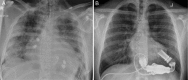

Herein we report a case of a 26-year-old gentleman with severe cardiomyopathy likely secondary to anabolic-androgenic steroid (AAS) abuse who received a HeartMate II (Abbott Laboratories, Abbott Park, IL) left ventricular assist device (LVAD) for rapidly deteriorating heart failure with hemodynamic compromise. Following 18 months on LVAD support, excellent recovery of ventricular function was achieved to allow for LVAD discontinuation. Given that active substance abuse is a contraindication to heart transplantation, few options remain for patients with AAS induced heart failure. Our case demonstrates that LVAD therapy can be an important intervention for bridging to candidacy, recovery or destination therapy.